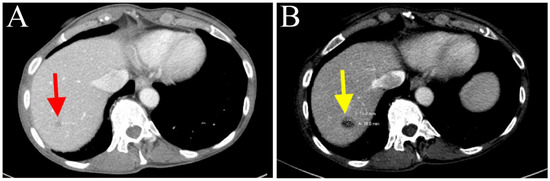

2. Case Description